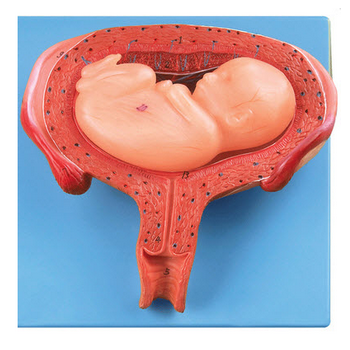

GD/A42005/5五個月胎兒模型產品介紹:1、尺寸:自然大,高16.5cm,寬12.5cm,厚7cm,共有14個部位指示標志。2、材質:進口PVC材料、進口油漆、電腦配色、高級彩繪有關GD/A42...